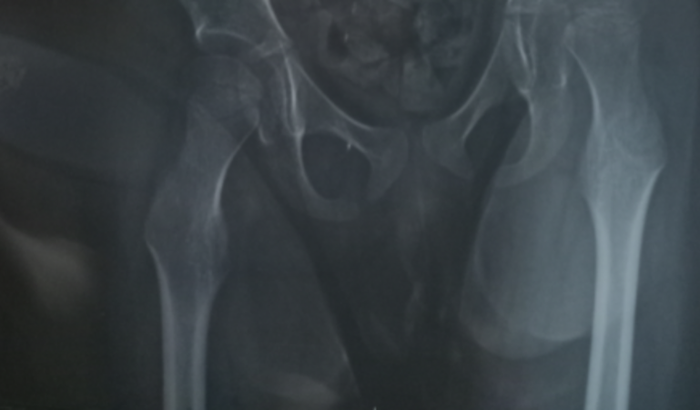

Olá amigos(as)sou Fernanda mãe da Maria Gabryela estamos pedindo a vaquinha na esperança de alcançar a meta de 40 mil reais para q ela possa faser uma cirurgia na bacia esquerda. Esta com uma abertura e precisa operar para voltar pro lugar .essa cirurgia é urgente e N estamos conseguindo pelo sus .devido ela sentir dor e um forte desconforto precisa ser feita com urgência e nós N temos condições financeiras de pagar ..td ajuda sera bem vinda .Ajudar faz bem .nós ajudem com o valor q vc puder ..